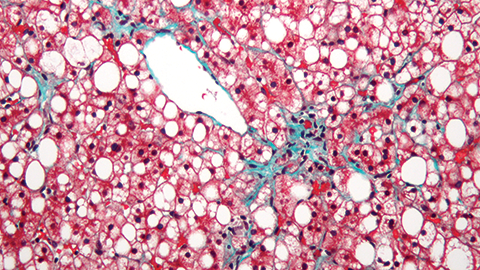

What is mitochondria’s role in non-alcoholic fatty liver disease? What’s the best way to differentiate embryonic and mesenchymal stem cells to use MSCs in therapy? How do fatty acids reduce melanin in tumor cells? Researchers tackle these questions …